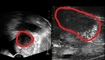

한림대학교강남성심병원(병원장 이동진)은 한림대학교의료원 최초로, 올해 1월 관상동맥 중재시술이 필요한 환자의 안전성과 치료 정확도를 높이기 위해 최신 AI 관상동맥 혈류분석 시스템 ‘뮤에프알(μFR AngioPlus Core)’을 도입했다. 관상동맥 질환은 심장에 혈액과 산소를 공급하는 관상동맥이 좁아지거나 막히는 질환으로, 혈류가 감소하면 가슴 통증을 유발하고 심한 경우 심근경색으로 이어질 수 있다. 문제는 관상동맥이 눈에 띄게 좁아 보이더라도 실제 혈류 장애가 없는 경우가 있는 반면, 겉보기에는 심하지 않아 보여도 혈류가 크게 떨어져 위험한 상황이 발생할 수 있다는 점이다. ▲ AI 관상동맥 혈류분석 시스템 뮤에프알에 대해 설명하는 한림대학교강남성심병원 순환기내과 조정래 교수 이에 따라 관상동맥 질환 치료에서는 혈관이 얼마나 좁아졌는지보다, 실제로 혈류 장애가 있는지를 정확히 판단하는 것이 무엇보다 중요하다. 그동안 실제 혈류 상태를 확인하기 위해 관상동맥 안으로 가느다란 와이어를 삽입하고 약물을 투여하는 침습적 검사가 시행돼 환자에게 부담이 될 수 있었다. 또한 관상동맥 협착이 70~80% 이상으로 보이면 중재시술을 결정하는 경우가 많았지만, 이는 시술